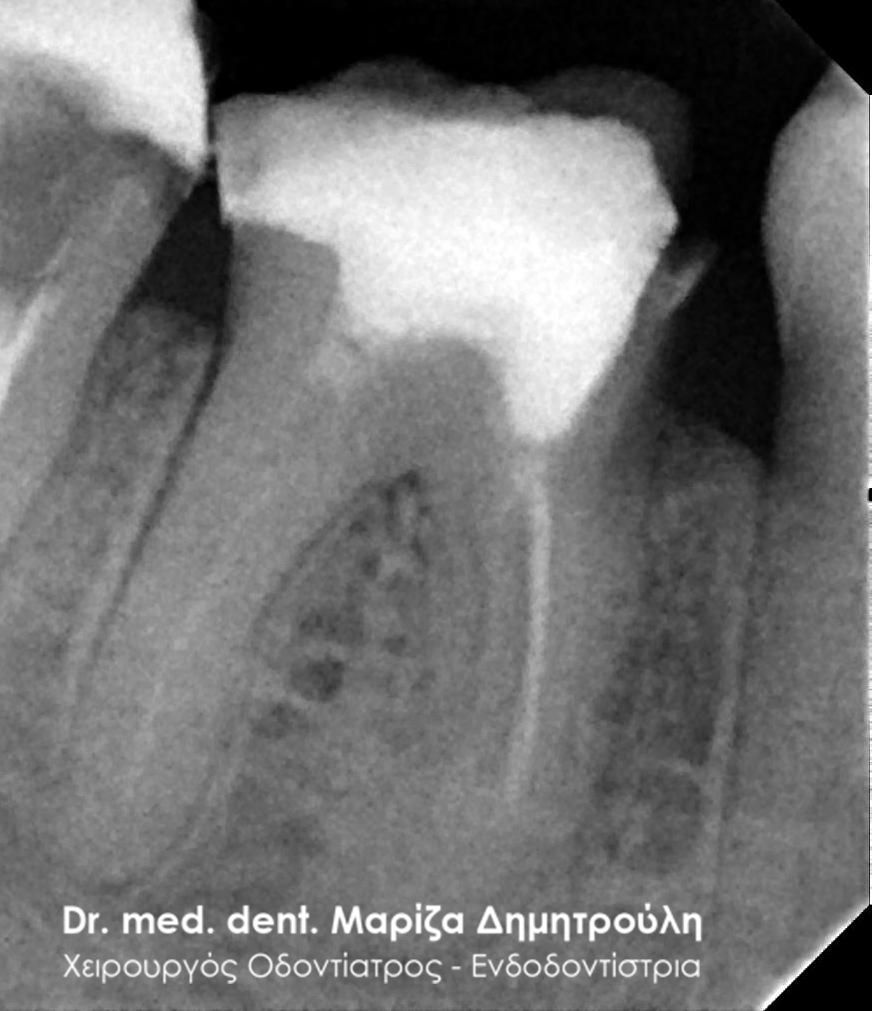

Η ασθενής προσήλθε με έντονο πόνο στο ιατρείο και είχε λάβει τις προηγούμενες μέρες αντιβίωση, εφόσον στην άνω αριστερή πλευρά της είχε οίδημα. Μετά την κλινική εξέταση διαπιστώθηκε η ύπαρξη ενός συριγγίου υπερώια μεταξύ των δύο άνω αριστερών γομφίων. Πραγματοποιήθηκε ακτινογραφία με την τοποθέτηση ενός κώνου γουταπέρκας για τη διάγνωση του υπαίτιου δοντιού, που είχε προκαλέσει την εμφάνιση του συριγγίου. Σύμφωνα με όσα αποκάλυψαν η κλινική και ακτινογραφική εξέταση ακολούθησε η έναρξη απονεύρωσης στο δεύτερο άνω αριστερό γομφίο, δεδομένου οτι είχε ένα βαθύ λευκό σφράγισμα ρητίνης που εκτεινόταν στο ύψος του νεύρου του δοντιού. Το δόντι είχε έντονα συμπτώματα πόνου κατά την επίκρουσή του.

Μετά την ολοκλήρωση της απονεύρωσης στο δεύτερο άνω αριστερό γομφίο το δόντι είναι ασυμπτωματικό. Η αποκατάσταση του δοντιού πραγματοποιήθηκε με λευκό σφράγισμα ρητίνης, εφόσον το έλλειμμα των οδοντικών ιστών ήταν μικρό και δε χρειαζόταν η προστασία του δοντιού με θήκη / στεφάνη δοντιού.

Σε δεύτερη φάση θα ακολουθήσει η επανάληψη απονεύρωσης στον πρώτο άνω αριστερό γομφίο, καθώς η απονεύρωση του δεν καλύπτει όλο το μήκος των ριζών του δοντιού και το δόντι μετά το πέρας της ενδοδοντικής θεραπείας συνεχίζει να πονά.

ΠΡΙΝ